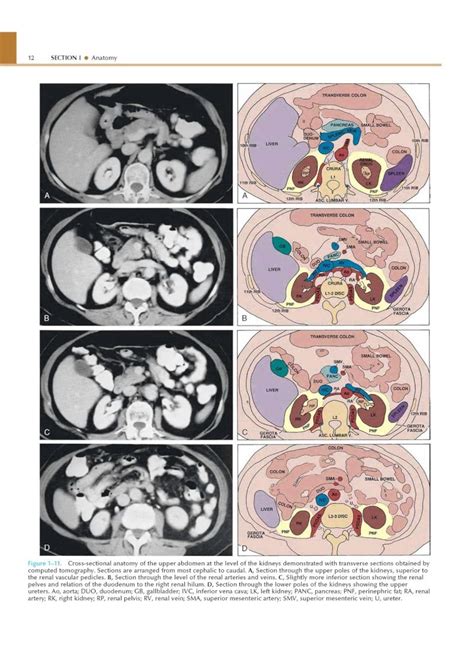

800×1132

fumed.forumactif.org

CT/TDM/SCAN…